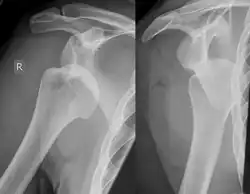

Anterior shoulder dislocation on X-ray with a large Hill–Sachs lesion

X-ray at left shows anterior dislocation in a young man after trying to get up from his bed. X-ray at right shows same shoulder after reduction and internal rotation, revealing both a Bankart lesion and a Hill-Sachs lesion.